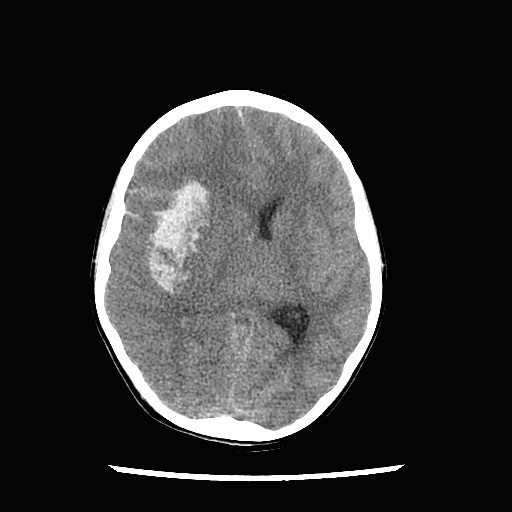

El radiólogo ya ha informado la imagen, y en el tiempo transcurrido ha solicitado una analítica sanguínea. El primer resultado que tiene es el relacionado con la coagulación.

Asume que, en relación al sangrado, presenta una coagulopatía de consumo. Sobre esta base, solicita los hemoderivados pertinentes y considera qué hacer a continuación